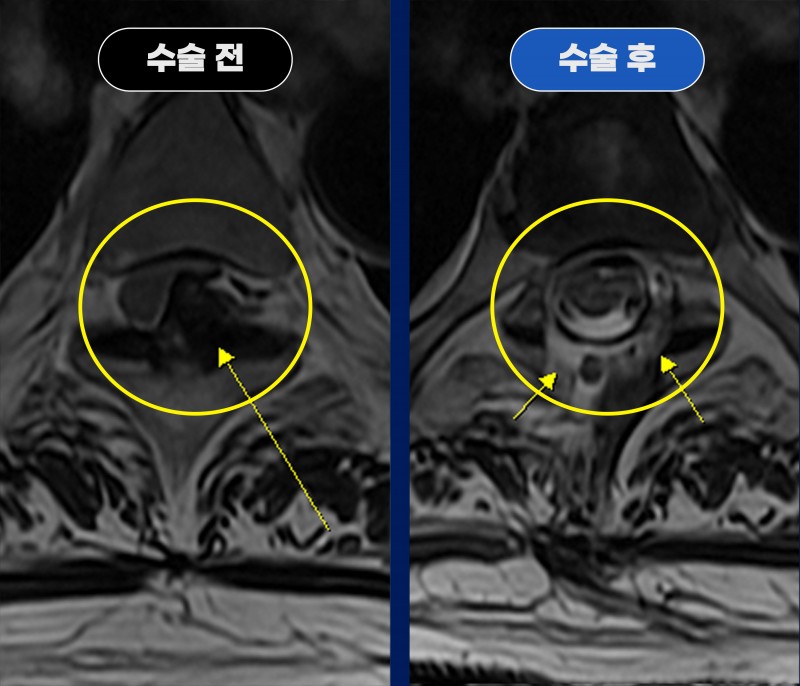

흉수증의 주요 원인 OLF(황색인대골화증) – T4/5 내시경 감압술 사례

흉추 T4/5 부위에서 척수를 강하게 압박하는 협착 소견

신경관의 절반 이상을 차지하는 병변

CT에서 황색인대골화증(OLF, OYL) 확인

좌측은 완전 골화, 우측은 진행 중인 석회화 단계

로 진단되었습니다.

수술 후 MRI에서

뾰족한 골화 병변 완전 제거, 척수 압박 해소, 신경관 충분히 확장된 모습 확인되었습니다.